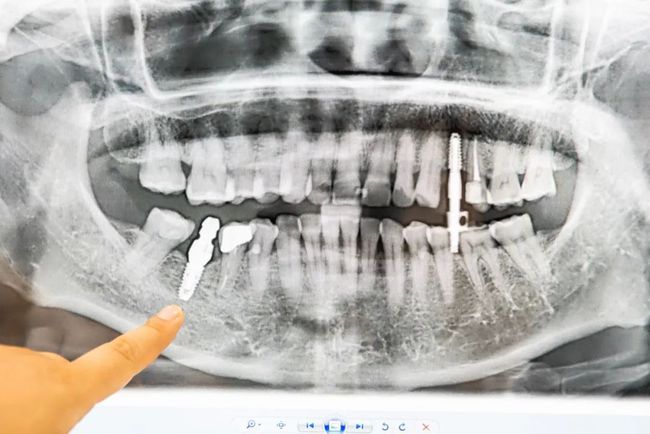

单牙缺失

种植后